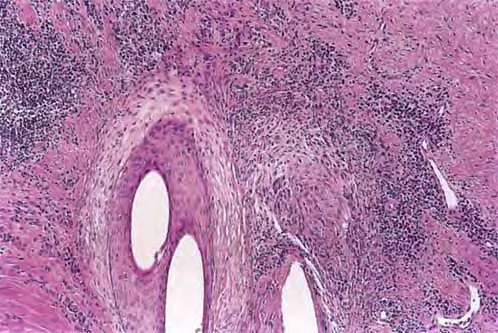

Diffuse large B-cell lymphoma = اللمفوما كبيرة الخلايا البائية المنتشرة